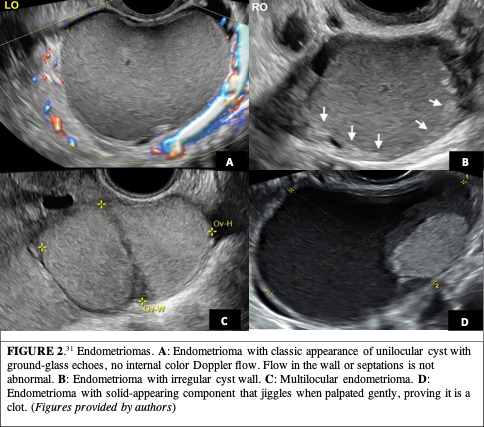

A continuación, evalúe los anexos: esto incluye no sólo la apariencia sino también la ubicación de los ovarios. El endometrioma se define como una masa quística que surge del tejido endometrial ectópico dentro del ovario. Los endometriomas son la manifestación ecográfica más reconocida de la endometriosis. La sensibilidad y especificidad de la detección por TVUS para endometriomas y endometriosis profunda (ED) es del 93% al 96% y del 79% al 94%, respectivamente. La presencia de un endometrioma aumenta significativamente la probabilidad de tener enfermedad rectosigmoidea. Además, hasta el 50% de los pacientes con DE tienen un endometrioma. La apariencia clásica del endometrioma es un quiste unilocular con ecos difusos y homogéneos en vidrio esmerilado debido a los desechos hemorrágicos. Alrededor del 87% de los endometriomas aparecen como quistes homogéneos de bajo nivel con apariencia de vidrio esmerilado (Figura 2A), aunque alrededor del 26% pueden tener paredes de quiste irregulares (Figura 2B)

Mientras que el 66% de los endometriomas son uniloculares, el 18% de los endometriomas en pacientes premenopáusicas tendrán una apariencia multilocular (Figura 2C). Alrededor del 17% de los endometriomas contienen componentes de apariencia sólida consistentes con coágulos (Figura 2D). Estos coágulos pueden moverse con el movimiento de la sonda, lo que demuestra que no son papilas fijas. En los casos en los que el generador de imágenes no esté seguro, debe describirse como un componente sólido y evaluarse con Doppler.

Es fundamental utilizar Doppler color para las lesiones anexiales. Los endometriomas no muestran color interno excepto en la pared o los tabiques, y es fundamental realizar Doppler color en cualquier lesión anexial para descartar el flujo de color interno (Figura 2A).